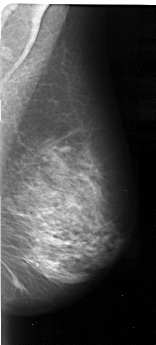

A_1097_1.LEFT_CC

LEFT_CC LINES 4441 PIXELS_PER_LINE 2491 BITS_PER_PIXEL 16 RESOLUTION 42 OVERLAY